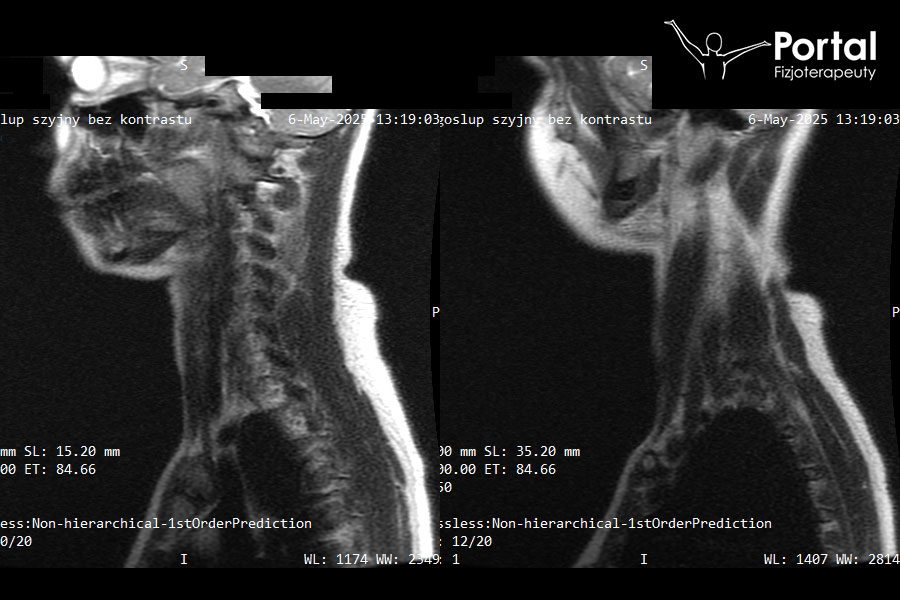

Aby ocenić, jak ustawia się lordoza szyjna, najczęściej wykonuje się badanie RTG odcinka szyjnego. Ukazuje ono z dużą dokładnością ułożenie wszystkich kręgów oraz obecność ewentualnych osteofitów czy zmian zwyrodnieniowych. Jednak chcąc jednocześnie ocenić obecność wypuklin kręgosłupa i przepuklin kręgosłupa, rekomenduje się wykonanie badania rezonansu magnetycznego (MRI).

Na poniższym badaniu obrazowym możemy zobaczyć przykładowe RTG odcinka szyjnego u jednego z pacjentów Centrum Fizjoterapeuty ze zmniejszoną lordozą szyjną: